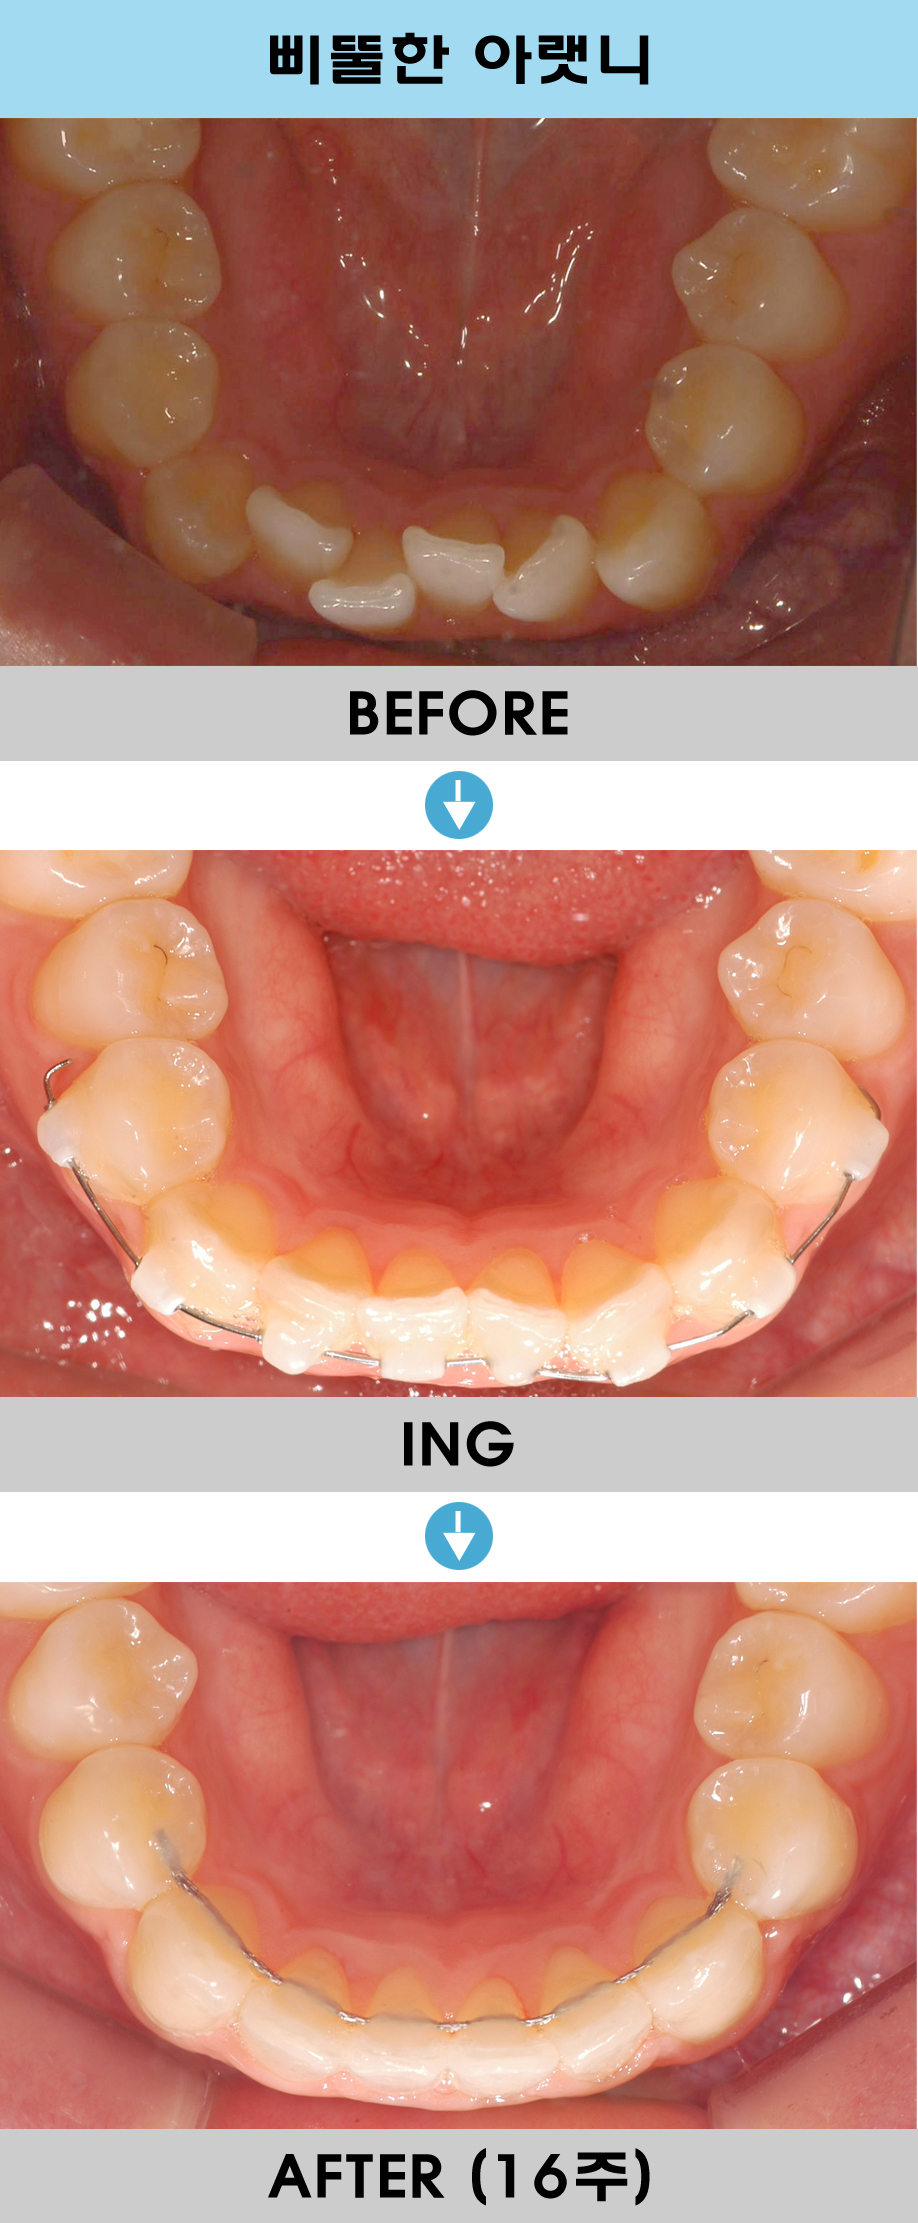

궁금한 내용은 아랫 앞니부분이 부분교정이 가능한지 궁금하신것 같습니다.

앞니가 삐뚤하기 때문에 치아표면에 착색이 되어 충치처럼 보입니다.(착색이지 충치는 아닙니다. 치아를 교정하면 치솔질이 용이하기때문에 착색이 생기는것도

예방되겠지요.)

교정기간은 5개월전후면 충분히 가능하고 비용은 150만원(월교정비는 4만원)입니다.